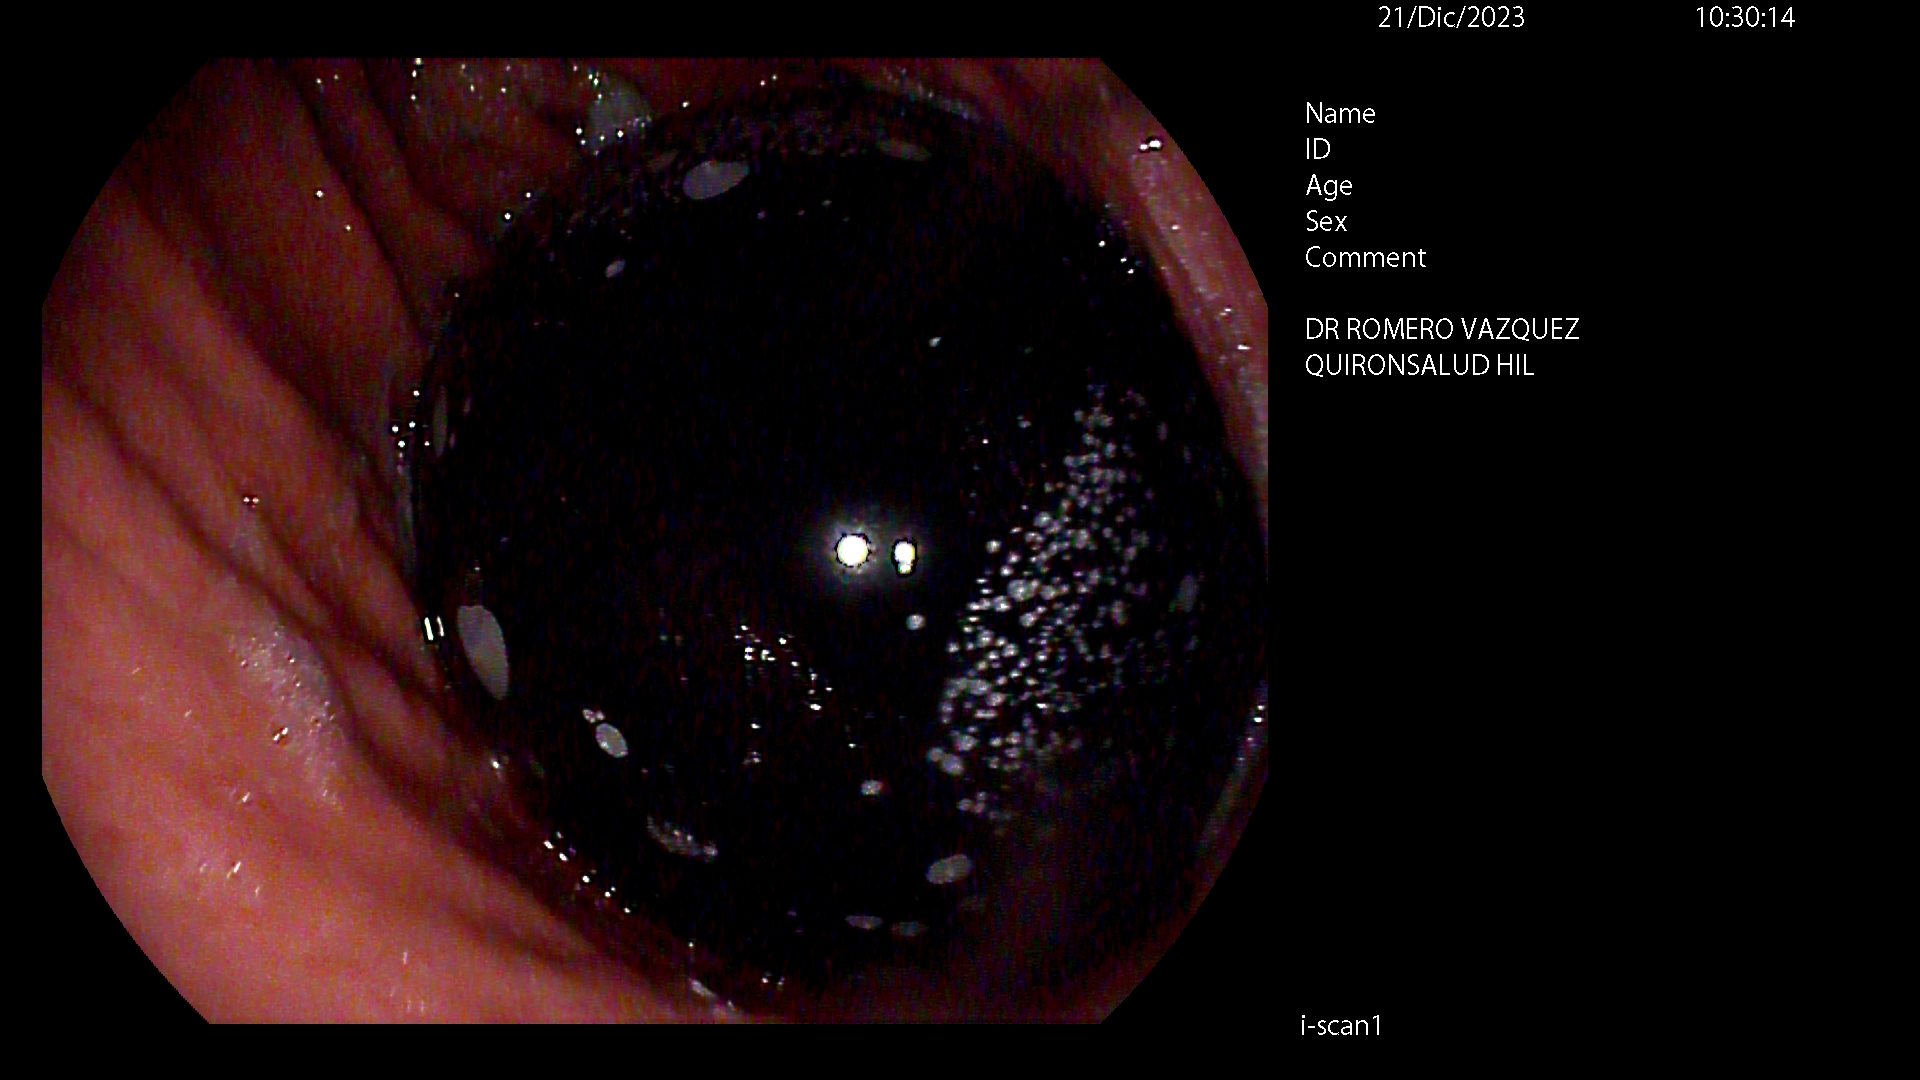

BALÓN INTRAGÁSTRICO

El balón intragástrico es un implante temporal de silicona, que rellenamos con suero, normalmente unos 500-600 cc, con un colorante (azul de metileno) para detectar cualquier posible anomalía futura (pérdida de contenido o rotura), una vez se aloja en el estómago y ocupa una parte importante del mismo. Esto genera dos mecanismos clave para aumentar la saciedad y por ello, perder peso:

- Ocupación de espacio: El dispositivo se aloja libremente en el estómago y genera ya de por sí una sensación de saciedad, ya que tiene entre 10 y 12 cm de diámetro.

- Enlentece la digestión de la comida: El balón dificulta el paso de la comida hacia el intestino, haciendo el proceso más largo en el tiempo. En condiciones normales, la comida tarda una hora aproximadamente en digerirse y pasar al intestino en donde se absorbe. En este caso, la comida permanece más tiempo en el estómago y hace que la saciedad se mantenga más tiempo, ayudando a no pasar hambre, sobre todo en el momento más crítico del día, que suelen ser las horas vespertinas.

Está indicado, como primera opción terapéutica, para pacientes con obesidad leve-moderada (IMC entre 30 y 35) o pacientes con IMC entre 35 y 40 que rechazan otros procedimientos.

Su colocación se realiza en la mayoría de las ocasiones por gastroscopia con sedación profunda administrada y controlada por anestesista, siendo una técnica ambulatoria (no precisa ingreso hospitalario) y su retirada, tras haber cumplido su función a los 6-12 meses, dependiendo de cada caso concreto, por gastroscopia con intubación y anestesista general, para minimizar los posibles inconveniente inherentes a la técnica, igualmente de forma ambulatoria.